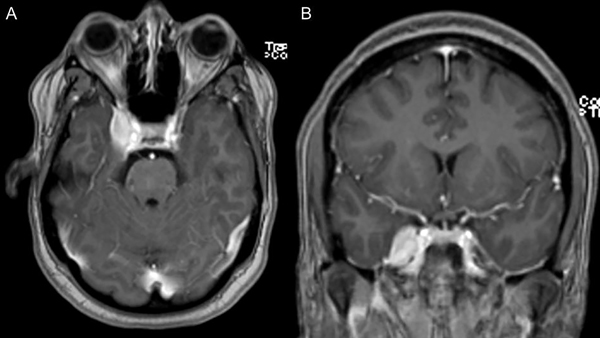

Paciente de 44 años, sin antecedentes de relevancia, que consultó por cuadro de dolor facial intenso, de tipo urente en territorio V1, V2 y V3 lado derecho. Se realizó Resonancia Magnética Nuclear (RMN) de cerebro en la que se observó lesión nodular extraaxial, con base de implantación en cara lateral del seno cavernoso derecho con intenso realce postcontraste; compatible en primera instancia con un meningioma con extensión a fosa temporal y cavum de Meckel (Figura 1). Realizó tratamiento farmacológico con Carbamazepina a dosis máxima y Gabapentin, sin mejoría de los síntomas. Posteriormente intercurrió con farmacodermia secundaria.

Figura 1. RMN de cerebro en secuencia T1 con contraste (preoperatoria) corte axial y coronal (A y B) que revela una lesión de masa bien delimitada que afecta al seno cavernoso y cávum trigeminal del lado derecho, que realza fuertemente a la administración de contraste con gadolinio.